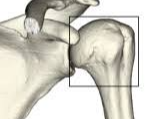

어깨에 골절이 발생하면 일상 전체가 마비되는 기분을 느끼는 것도 무리는 아닙니다. 특히 쇄골, 상완골 근위부, 견갑골 부위에 골절이 생기면 수술이 필요하며, 수술 이후의 재활과 물리치료는 단순히 통증을 없애는 것을 넘어, 관절 가동 범위의 회복과 장기적인 기능 정상화를 위한 핵심 단계입니다. 또한 어깨 골절 수술 이후 본격적으로 시작되는 재활 치료와 도수치료의 현실적인 문제는 ‘비용’과 ‘보험 적용 여부’입니다.